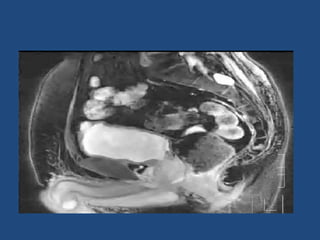

Prostate cancer is the second most common cancer globally, with varying incidence rates influenced by geography and lifestyle changes. In India, prostate cancer cases are rising due to urban migration and increased medical awareness, with current rates approaching those in Western countries. Treatment options vary by stage, including watchful waiting, surgery, radiation therapy, and hormonal treatment, each tailored to patient-specific factors.